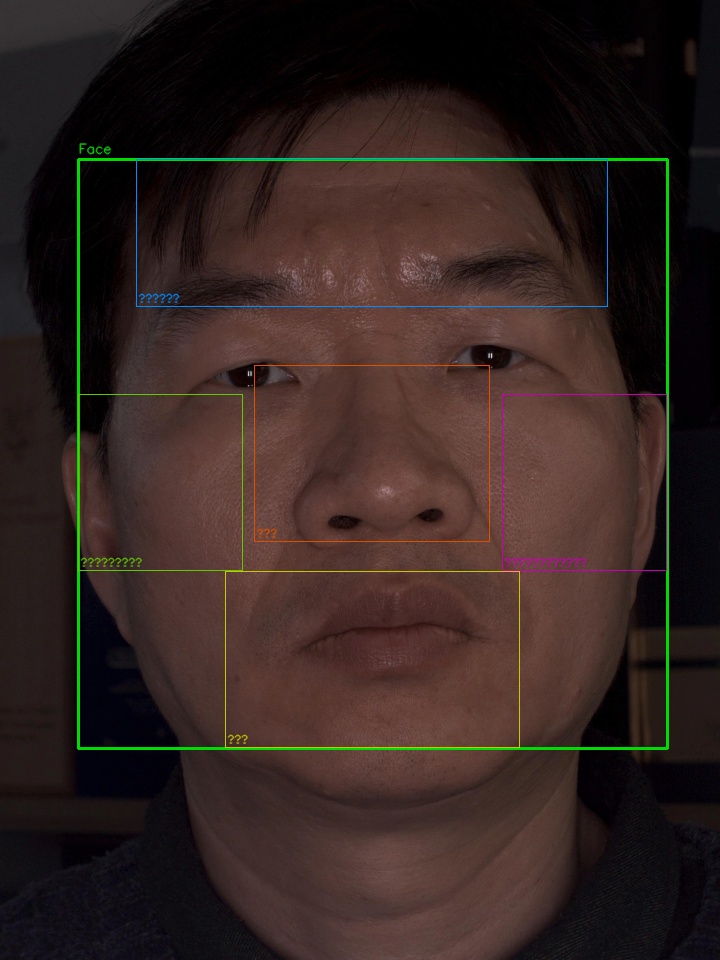

이마